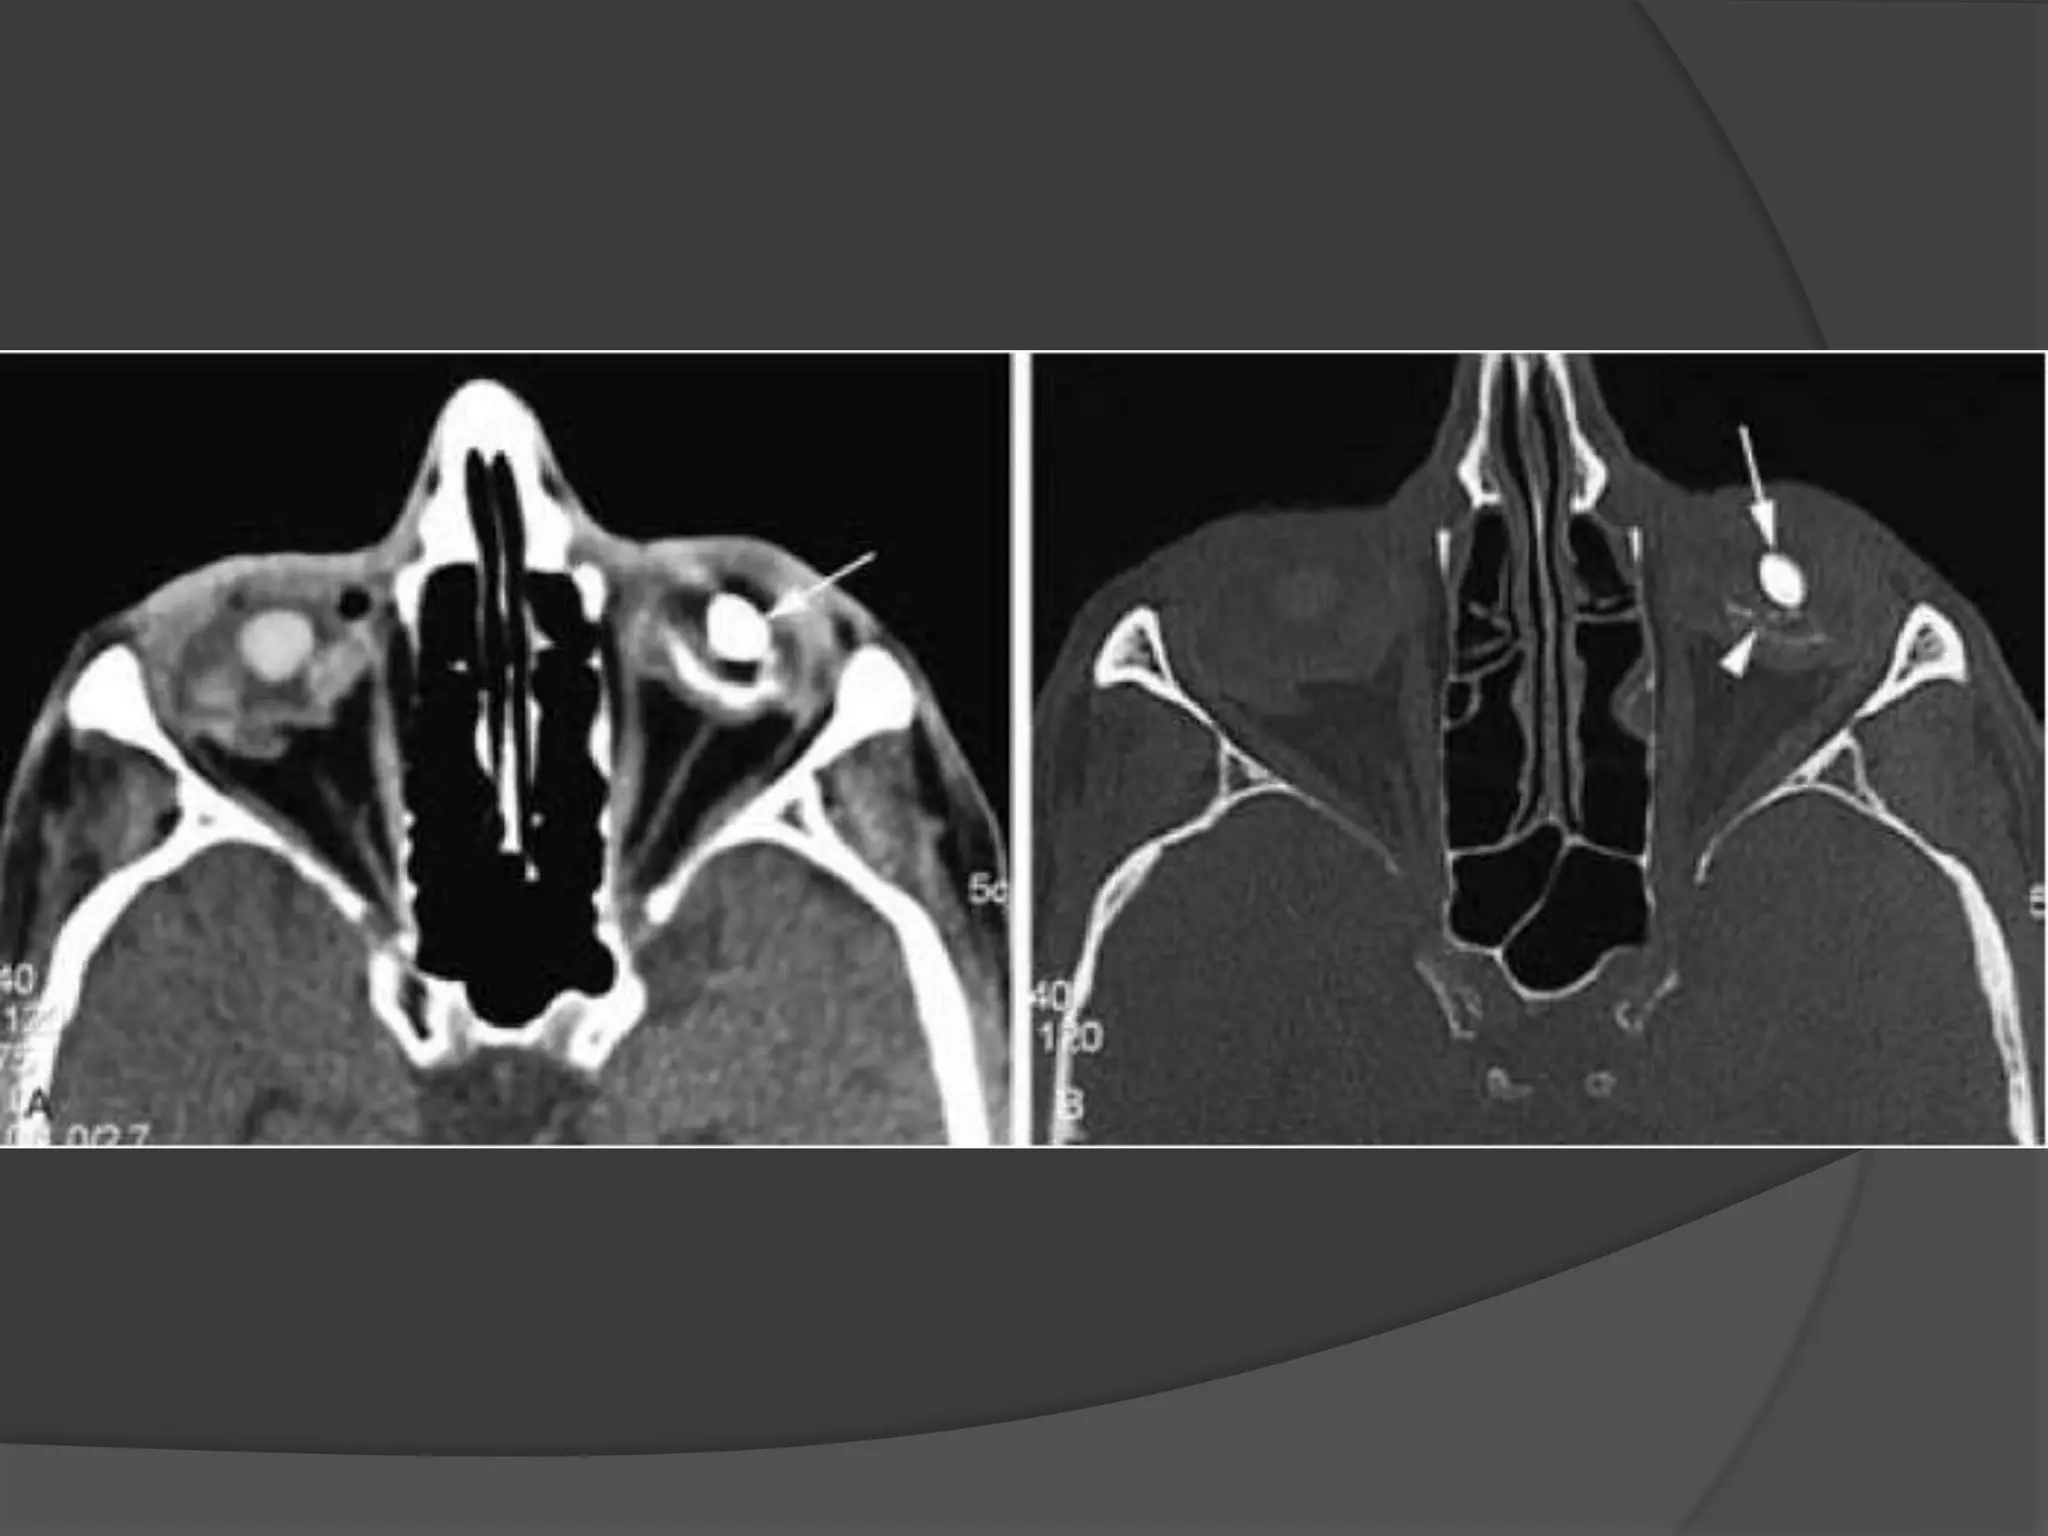

Rhabdomyosarcoma. CECT image

(A) Orbits demonstrates right proptosis due to large, lobular, intraorbital

mass.

(B) Image at lower level demonstrates invasion of right maxillary

sinus (asterisk) as well as extension through lateral orbital wall (arrow),

consistent with the aggressive nature of this tumor.